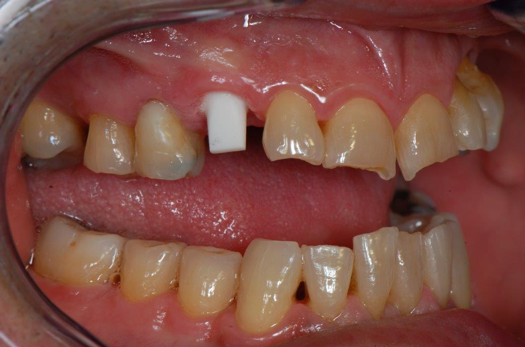

Fig 22. 12 weeks postoperatively.

Figure 22

Sutures were removed 2 weeks after surgical implant placement, and the patient was instructed to continuously wear his Essix-style retainer for 12 weeks. The retainer was worn while eating during the 12-week period. The patient returned at 12 weeks for soft-tissue and implant-bone evaluation (Figure 22). At this appointment, minimal lingual soft-tissue manipulation was performed by gingival abrasion to the keratinized soft tissue and an aluminum chloride gel was placed.

Figure 23 showed an example of gingival soft tissue creeping occlusally and over the lingual gingival margin of the one-piece ceramic dental implant. This supragingival migration was caused by the exceptional biocompatibility due to the acid-etched surface of the implant, a one-piece implant that prevents bacterial colonization that one may find with two-piece metal-implant systems.